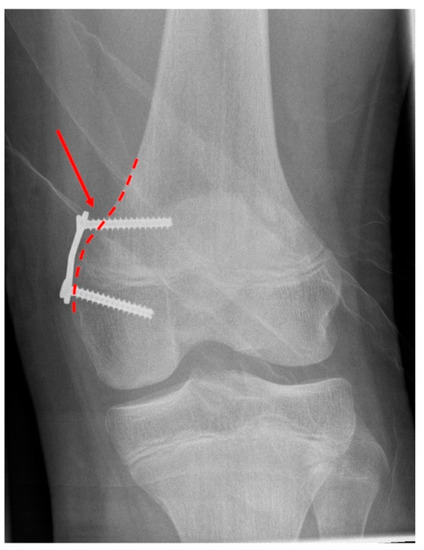

2.2. Radiographic Measurements

| Plate position in relation to the physis | 0.049 | ||

| centered | 28 (77.7%) | 14 (77.8%) | |

| epiphyseal | 6 (16.7%) | 0 (0.0%) | |

| metaphyseal | 2 (5.6%) | 4 (22.2%) | |

| Plate position in relation to the shaft axis of femur/tibia (°) | 2.1 (11.2) | 5.9 (13.5) | 0.31 |